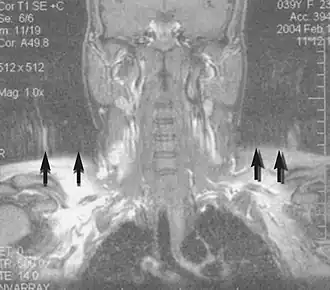

Angiography

Magnetic resonance angiography (MRA) generates pictures of the arteries to evaluate them for stenosis (abnormal narrowing) or aneurysms (vessel wall dilatations, at risk of rupture). MRA is often used to evaluate the arteries of the neck and brain, the thoracic and abdominal aorta, the renal arteries, and the legs (called a "run-off"). A variety of techniques can be used to generate the pictures, such as administration of a paramagnetic contrast agent (gadolinium) or using a technique known as "flow-related enhancement" (e.g., 2D and 3D time-of-flight sequences), where most of the signal on an image is due to blood that recently moved into that plane (see also FLASH MRI).[53]